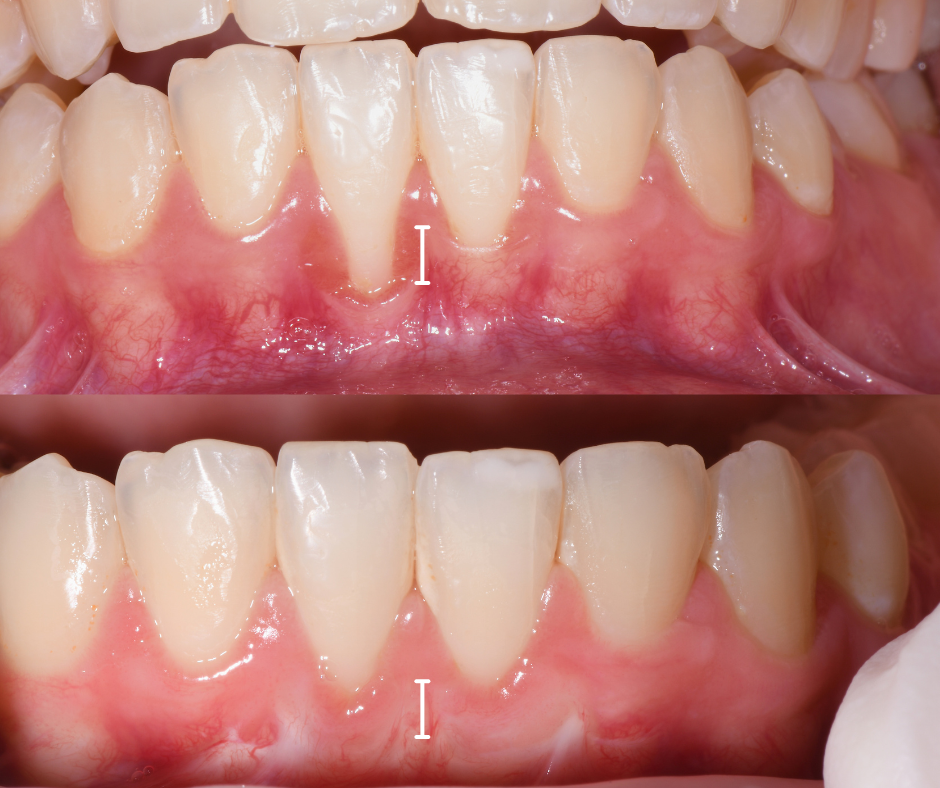

Le Tasche Gengivali

Questo è un segnale che spesso comunichiamo noi dentisti durante le visite. Usiamo uno strumento chiamato sonda parodontale - praticamente un piccolo righello metallico - che ci permette di misurare la profondità dello spazio tra gengiva e dente.

Se la sonda scende in profondità (oltre i 3-4mm), significa che lì sotto l'osso si è riassorbito. In quella zona si accumulano cibo e batteri che continuano a distruggere i tessuti circostanti.

I primi risultati si vedono dopo 2-3 mesi: riduzione dell'infiammazione, meno sanguinamento, chiusura parziale delle tasche.